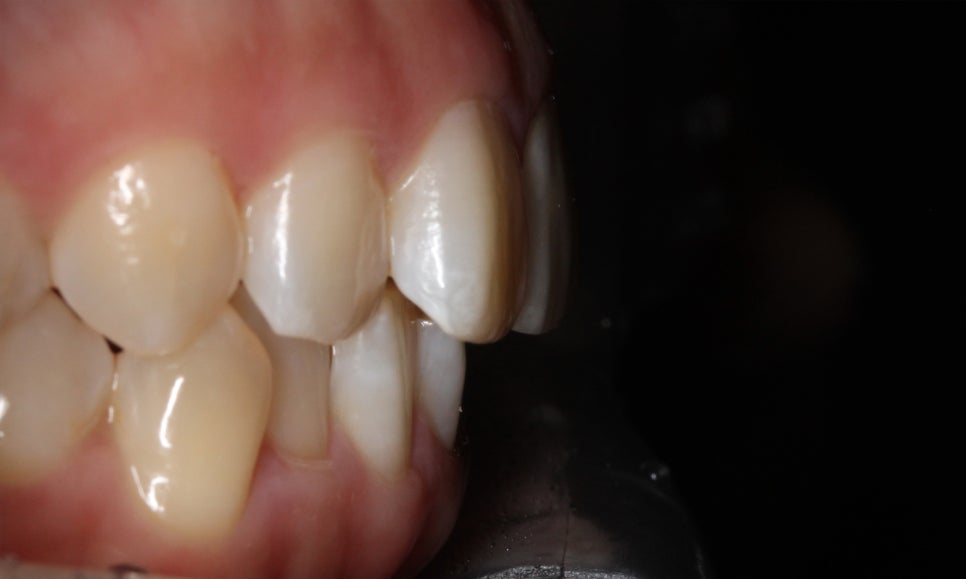

송곳니교정 전 전치부의 overjet 사진을 확인해보면

상악 중절치가 약간 돌출되어 있는 것을 확인할 수 있는데요,

아랫니도 미세하게 crowding이 발견되어 송곳니의

덧니 증상을 해결하면서 전치부 치열을

가지런하게 만들어야 할 것으로 보입니다.